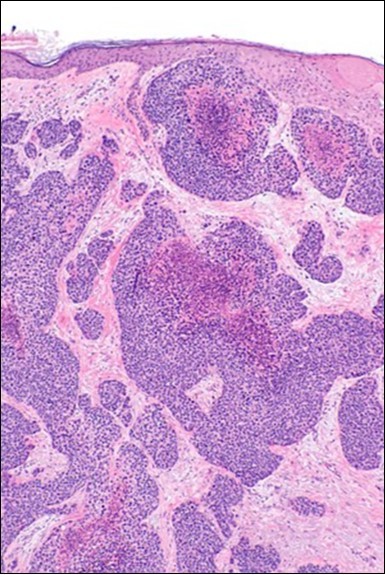

Granular arrangement of malignant cells and intercellular bridges are conspicuous with the demonstration of nuclear atypia, pleomorphism, prominent mitosis and tumour necrosis. A peripheral palisade is discernible within the cellular aggregates. Mitotic figures are common and can be quantified as up to 12 mitosis/ high power field. Tumour differentiation can prominently be of the ductal category with the demonstration of intra-cytoplasmic lumina. Comedo type tumour necrosis is evident along with foci of squamous differentiation The neoplasm is reactive to periodic acid Schiff ‘s (PAS) stain. (Figure 1, Figure 2, Figure 3, Figure 4, Figure 5, Figure 6, Figure 7, Figure 8, Figure 9, Figure 10, Figure 11, Figure 12, Figure 13.

Figure 1.Solid aggregates of tumour cells and duct structures in eccrine porocarcinoma (14).

Eccrine porocarcinoma is an infiltrative, high grade tumour which is contiguous with superimposed epidermis, depicts a partially lobular architecture and a diameter usually exceeding > 90 millimetres. An endophytic pattern of tumour evolution is elucidated with invasion of deep reticular dermis and subcutaneous tissue 5, 6.

The neoplasm is composed of lobules of aberrant epithelial cells configured in cords with incrimination of the dermis and epidermis.. Malignant cells congregate within the epidermis or infiltrate the dermis, especially in the primary tumour. Tumour cells within tumour aggregates display a well demarcated cellular outline and appear distinct from encompassing squamous cells. Numerous tumour cell clusters demonstrate a cystic lumen. Prominent epidermal acanthosis is discerned on account of tumour cell proliferation 6, 7.